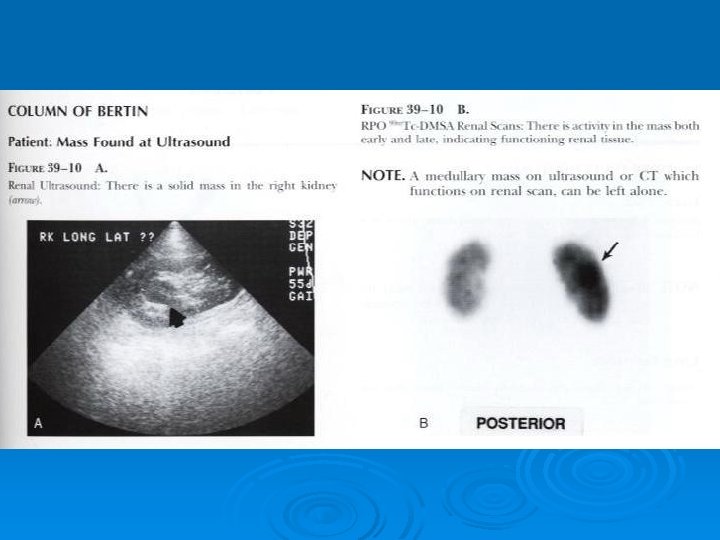

DMSA Renal scan; Clinical applications; Ø Ø Ø Ø Ø Renal size, shape and location Renal cortical assessment. Determining DRF (most accurate noninvasive method) Infectious disease and distinguish upper from lower UTI(Early detection and follow up of pyelonephritis; most sensitive, 95% Vs 76%) Follow up of patients(serial scans) Congenital renal anomaly(Ectopia, . . ) Vascular lesions (infarct) DDx of pseudomass from SOL. Renal trauma Confirm the total absence of function in dysplastic kidney

Renal Cortical Scintigraphy Congenital Anomalies Ø Agenesis Ø Ectopy Ø Fusion (horseshoe, crossed fused ectopia) Ø Polycystic kidney Ø Multicystic dysplastic kidney Ø Pseudomasses (fetal lobulation, hypertrophic column of Bertin)